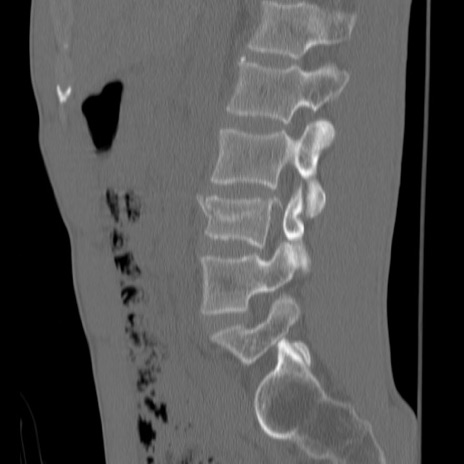

症例3 腰椎CT(矢状断像)

腰椎CT